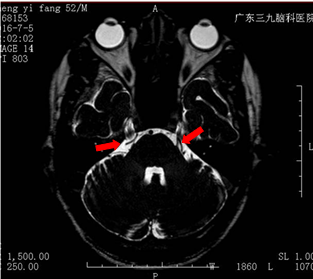

为了进一步治疗自己的疼痛问题,郑先生来到广东三九脑科医院。微侵袭神经外科的医生诊断其为:右侧三叉神经痛,MR检查可见双侧三叉神经颅内段与周围一小血管关系密切。

MR可见双侧三叉神经上骑跨的小血管(箭头所示)